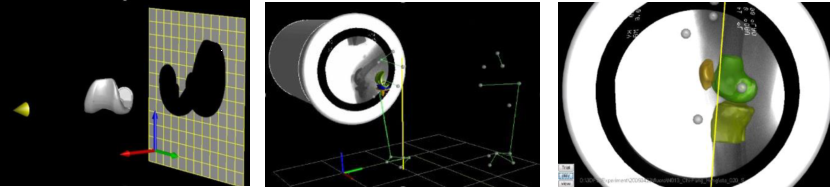

(3) Imaging Tracking Technique 影像追踪技术

Accurate Dynamic Joint Kinematics 精准关节运动学

Fluoroscopic Tracking Technique (2D-3D registration) 荧光检查追踪技术(2D-3D配准)

图注:开发医学影像技术评估活体髋与假体关节功能

图注:开发利用3维数字化骨骼模型与2维动态X光配准的技术,实现非侵入式的精准在体关节运动测量